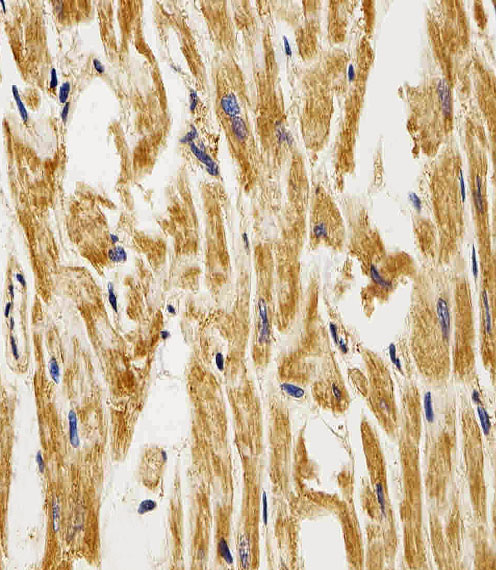

Immunohistochemical analysis of paraffin-embedded H. heart section using FABP3( APC00101G). APC00101G was diluted at 1:25 dilution. A peroxidase-conjugated goat anti-rabbit IgG at 1:400 dilution was used as the secondary antibody, followed by DAB staining. |